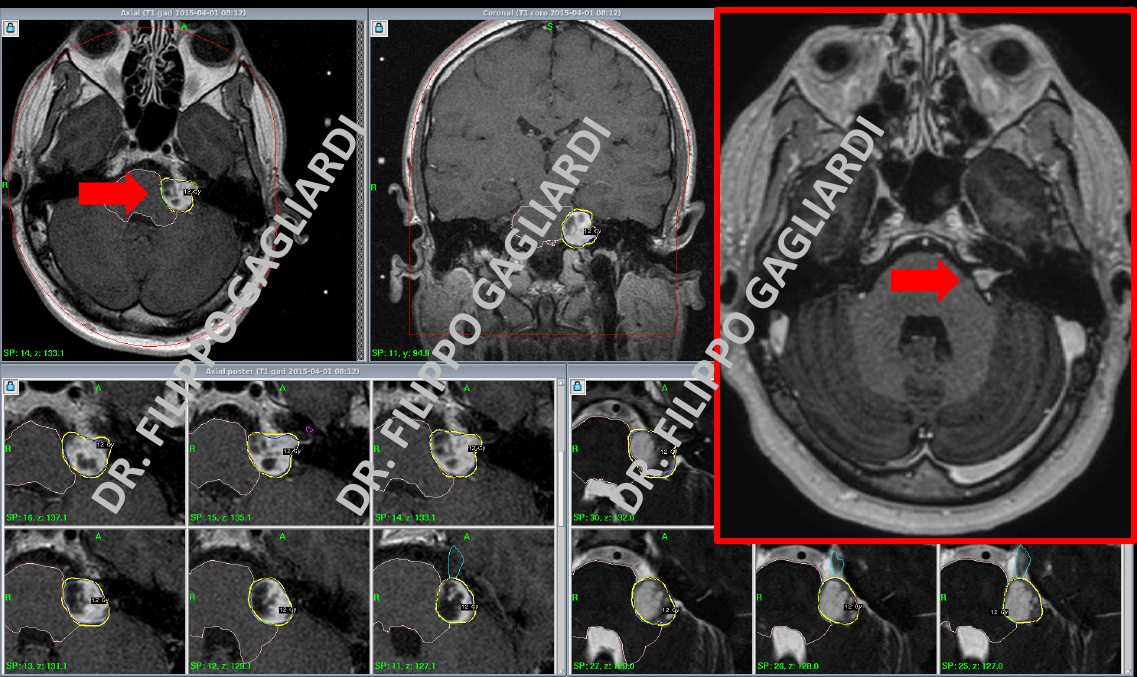

Nella foto si vede li Dr. Gagliardi durante la preparazione di un piano di trattamento Gamma Knife. La lesione è contornata da una linea gialla che corrisponde alla visualizzazione della geometria del campo di radiazione (freccia rossa). Di seguito un caso clinico.

Caso di neurinoma dell’VIII nervo cranico di sinistra trattato con radiochirurgia stereotassica in una donna giovane venuta all’attenzione per un calo progressivo dell’udito. La freccia rossa in alto a sinistra mostra le lesione il giorno del trattamento. La lesione è contornata da una linea gialla che corrisponde alla visualizzazione della geometria del campo di radiazione. Come si può vedere la radiazione è estremamente conformata, il che significa che riproduce in modo quasi perfetto la geometria del tumore minimizzando la dose ai tessuti circostanti. Nel riquadro in rosso si vede la RM di controllo della Paziente a 4 anni dal trattamento: la lesione è praticamente scomparsa (freccia rossa in alto a destra). La Paziente non ha presentato alcuna complicanza.